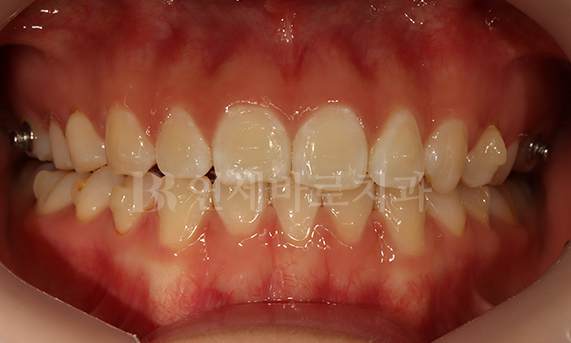

돌출입 교정 CASE

-